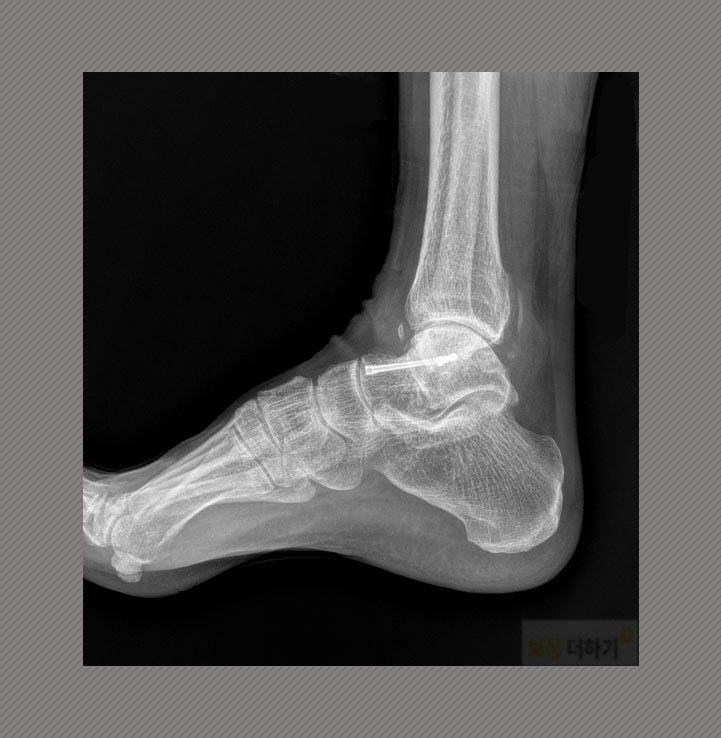

오른쪽 발목을 심하게 다쳤고, 거골 개방성 골절 및 탈구 진단받으셨어요. (↓거골 위치는 다음과 같습니다.)

거골 골절 형태도 개방성으로, 어긋난 뼈가 살갗을 뚫고 나온 좋지 않은 상태인데 주변의 인대까지 손상을 입었으니 치료와 회복이 쉽지 않았음을 예상할 수 있습니다. 뼈가 안정적으로 붙고 후유증이 최대한 남지 않도록 수술을 받으셨어요. (관혈적 골 정복술, k-wire 금속 강선, 금속나사 고정술, 복합 피부이식술 등이 시행되었습니다.)